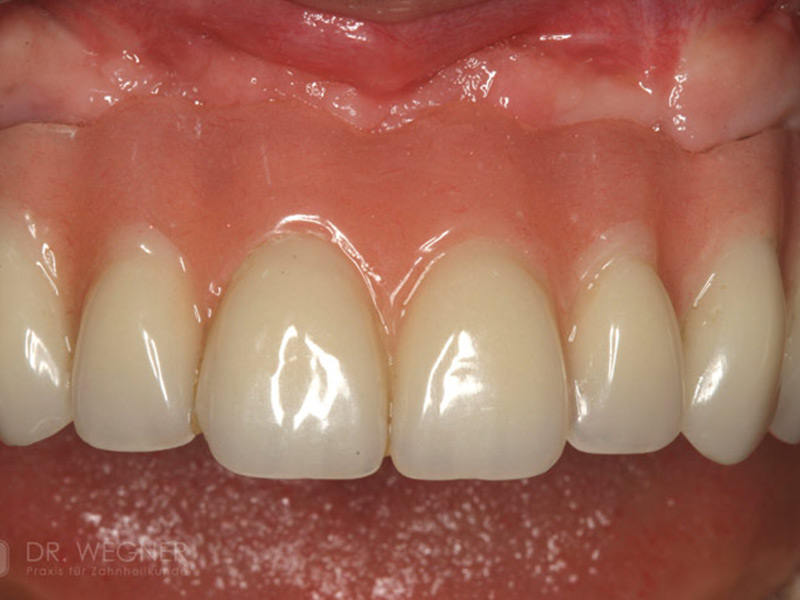

Zahnimplantate werden anhand von moderner virtueller 3D-Planung passgenau geplant und inseriert. Der Vorteil von Implantaten besteht darin, dass festsitzender ästhetischer Zahnersatz auch in solchen Fällen realisiert werden kann, in denen sonst nur herausnehmbare Prothesen möglich wären. Zudem ist im Gegensatz zur Brückenprothetik kein Beschleifen der Nachbarzähne notwendig.

Unter dentalen Implantaten versteht man im allgemeinen eine Schraube, die dort, wo ein oder mehrere Zähne verloren gegangen sind, in den Kieferknochen "eingepflanzt" wird. Diese Therapieform der Implantologie hat sich in den letzten Jahren zu einem alltäglichen Therapieverfahren in der Zahnheilkunde entwickelt. Wissenschaftliche Untersuchungen zeigen hierfür eine Erfolgsquote von i. d. R. 80-98 % über 10 Jahre. Verglichen mit anderen zahnärztlichen Maßnahmen gibt es nahezu keine andere Therapie mit derart guten Erfolgsaussichten. Auch eine Verbesserung der Lebensqualität wird durch implantatgetragenen Zahnersatz laut klinischer Studien erreicht.

Mittlerweile hat sich die Implantologie zu einem alltäglichen Therapieverfahren mit sehr guten Erfolgsaussichten in der Zahnheilkunde entwickelt. Bei guter Mundhygiene und regelmäßigen Kontrolluntersuchungen können fachmännisch gesetzte Zahnimplantate ein Leben lang halten.